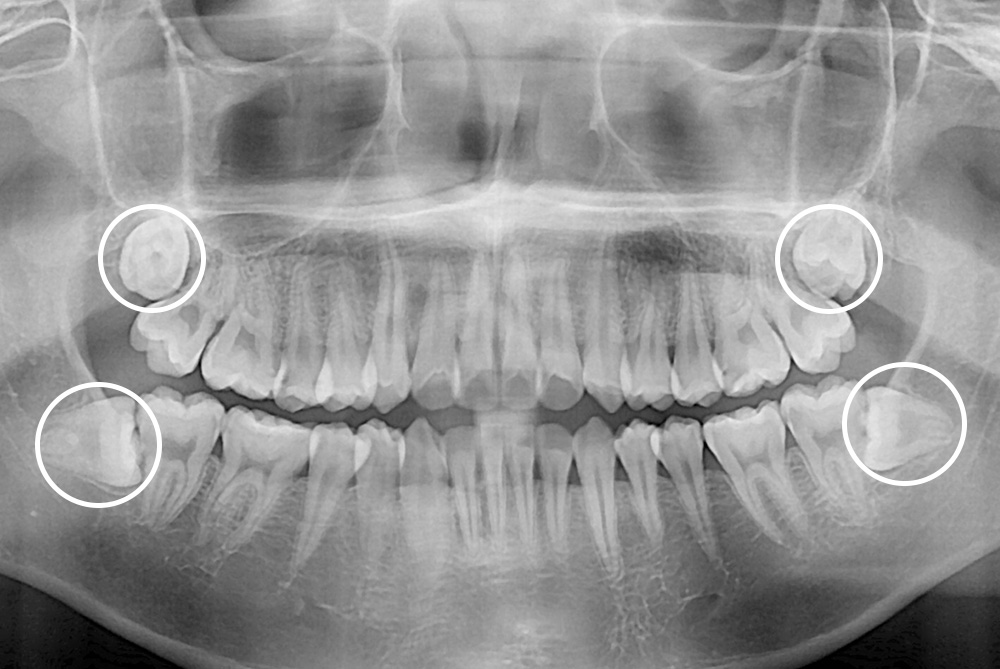

[사랑니] 매복 사랑니 발치

치료후 : 2018-11-23

세종치과는 구강악안면외과학 박사이신 원장님이 발치하는 치과입니다.